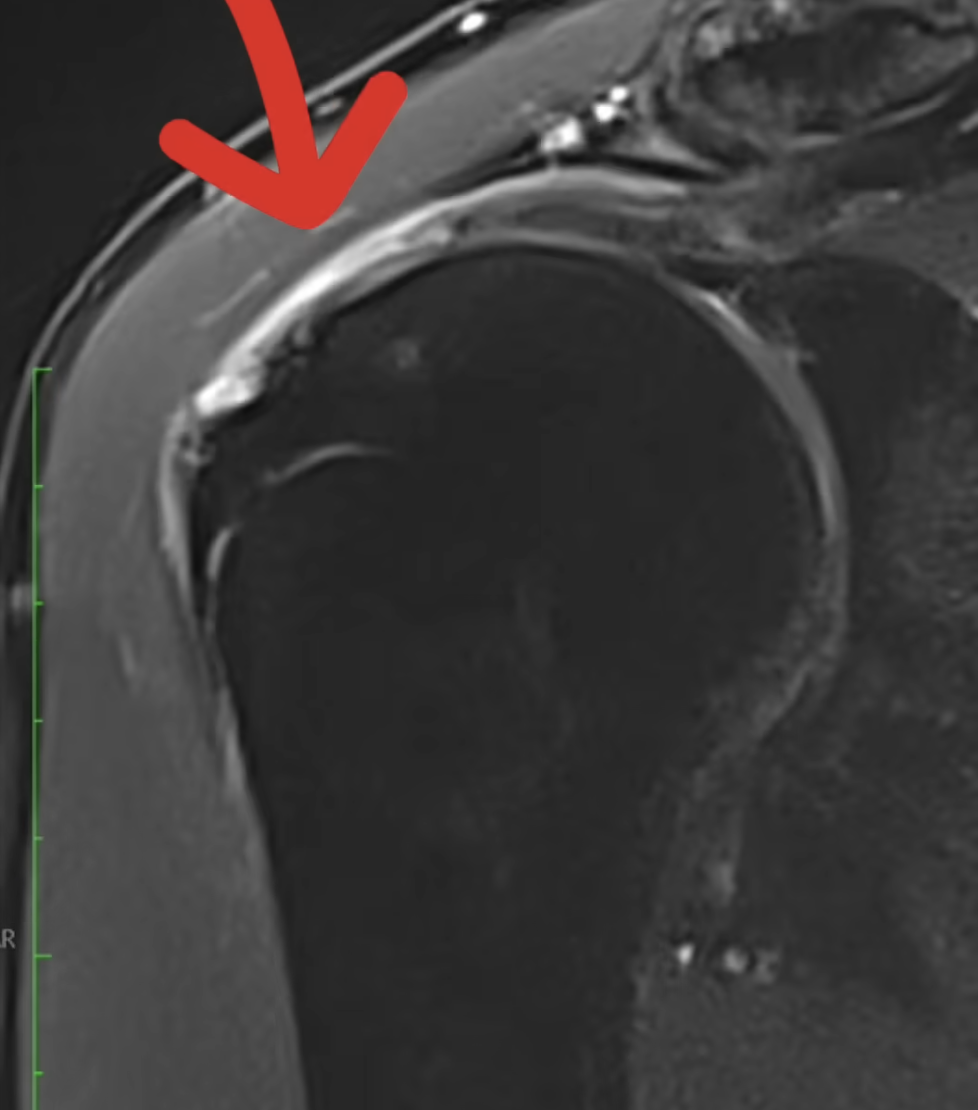

Qu’est-ce qu’une rupture de la coiffe ?

Quels paramètres sont analysés par un chirurgien devant une rupture de la coiffe des rotateurs ?

3 paramètres importants analysés par votre chirurgien devant une lésion de la coiffe.